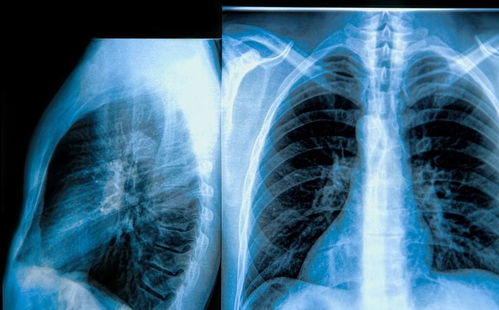

肿瘤心脏积液处理办法

1. 若积液是由恶性肿瘤的转移引起,如肺癌、乳腺癌等,我们将采取化疗、放疗或靶向治疗等策略,从源头上控制肿瘤的进展,减少积液的生成。

2. 对于中大量积液或心包填塞的患者,我们需要紧急行动。心包穿刺引流可以快速缓解他们的呼吸困难、低血压等症状。对于那些反复积液或穿刺无效的患者,我们会考虑进行心包开窗术,通过手术将积液引流至胸腔或腹腔。